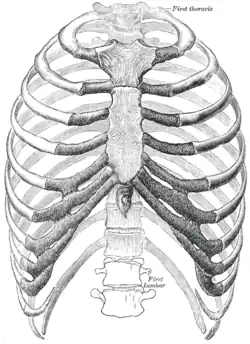

Brustkorb

Der Brustkorb oder Thorax (altgriechisch θώραξ ‚Brustpanzer‘, Plural Thoraces) der Wirbeltiere ist in der Anatomie ein Abschnitt des Rumpfes. Die Wand des Brustkorbs wird von Brustwirbelsäule, Brustbein und Rippen (knöcherner Thorax, Teil vom Skelett des Menschen) sowie von Muskulatur gebildet. Er umschließt die Brusthöhle (Cavum thoracis) und, aufgrund der Kuppelform des Zwerchfells, auch den oberen (bei Tieren vorderen) Teil der Bauchhöhle. Die am Thorax außen und innen ansetzende Atemmuskulatur ermöglicht die Atmung bei landlebenden Wirbeltieren.

Der Zugang zum Brustkorb wird von der oberen und unteren Thoraxapertur gebildet. Der Brustbeinwinkel (Angulus sterni) liegt beim Menschen in Höhe der 2. Rippe. Die knorpelige Spitze der 11. Rippe kann seitlich, die der 12. Rippe hinten getastet werden. Der untere Winkel (Angulus inferior) des Schulterblatts (Scapula) liegt in Höhe der 7. Rippe und des 7. Zwischenrippenraumes (Interkostalraum).